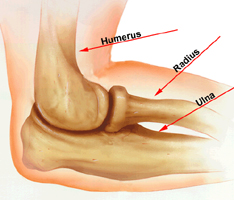

Normal elbow anatomy. Bones of the elbow.

(Reproduced with permission from Tashjian RZ, Katarincic JA: Complex Elbow Instability. J Am Acad Orthop Surg 2006;14:278-286.)

Three bones come together to make up the elbow joint. The humerus is the bone in the upper arm. Two bones from the forearm (the radius and the ulna) form the lower part of the elbow. Each of these bones has a very distinct shape. Ligaments connected to the bones keep all of these bones in proper alignment.